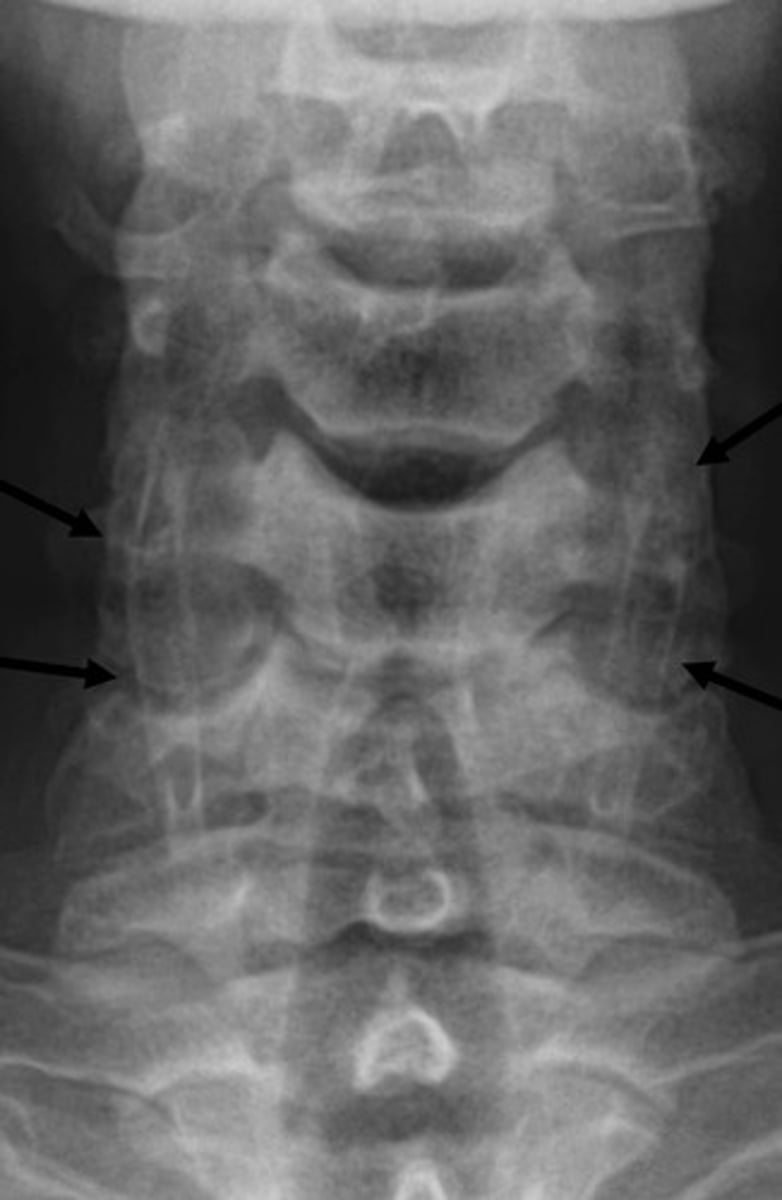

Imaging Findings of Incomplete Segmentation

— Hyperplastic transverse process ("batwing" appearance)

— Hypoplastic disc

— Possible accesory joint formation

— Occasional accessory joint degeneration

Image example of sacralization of L5